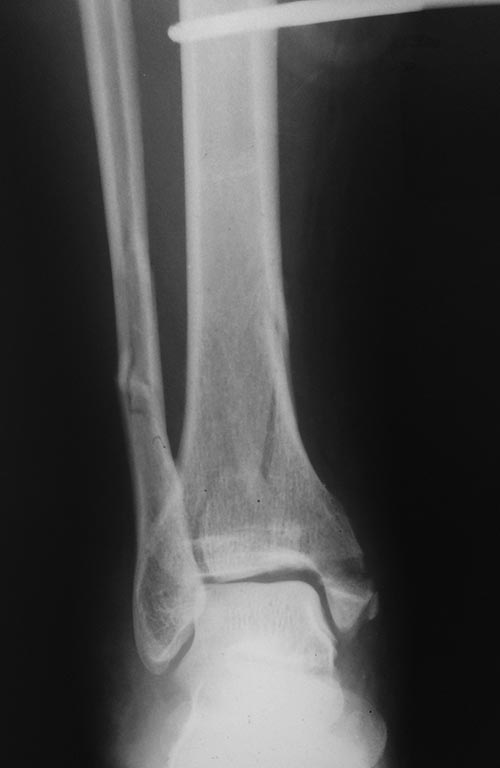

Травма голеностопного сустава 44С3 помогите определиться с оперативной тактикой

Пациентка 49 лет, повышенного питания, получила травму поскользнувшись на улице, сразу поступила к нам,

при поступлении наложен стержневой авф, прошло 5 суток, отек умеренный, будем готовы к пятнице к операции. Думаем 1/3 трубка на наружную, фиксация синдесмоза, вопрос в медиальной лодыжке и заднем крае, коллеги, подскажите какой фиксатор предпочтительнее, заранее благодарен, Дмитрий.

P.S: провести кт нет возможности и ни под каким углом(

С таким внутрисуставным характером перелом думаю лучше рассматривать как "пилон", а не "лодыжечный", т.е. 43С.

В данном случае повреждение межберцового синдесмоза выражается в отрыве заднего края б/б кости, восстановив который, вы компенсируете повреждение ДМС. Для восстановления метафиза с медиальной стороны лучше будет положить пластину (опорная, противоскользящая). Внутреннюю лодыжку можно винтами, можно по Веберу - это зависит от ваших ресурсов.

Все вместе это, тем не менее, перелом пилона, ближе к 43B1. КТ все-таки стоило бы изыскать возможность сделать. Лучше после наложения временного наружного фиксатора.

Классификация OTA/AO строится на морфологии повреждения, что определяет лечение, а не на механизме травмы. Который, конечно, довольно точно иногда может быть косвенно предположен. Скорее, надо спрашивать, почему возникает желание назвать это 44, если 44 - это переломы лодыжек. Да, здесь есть перелом внутренней лодыжки, но это же не все.

А здесь линия перелома tibia распространяется до границы с диафизом, если не выше, и связанной с диафизом остается только латеральная стенка дистального отдела tbia. То есть по характеру повреждения это никак не перелом лодыжек, а именно перелом пилона.

Соответственно, фиксация нужна не как при переломах лодыжек (треть трубки на малоберцовую+винт в задний край+спицы и проволока или винты во внутреннюю лодыжку), а как при переломе пилона - еще и опорная пластина на дистальный отдел tibia, или аппарат.